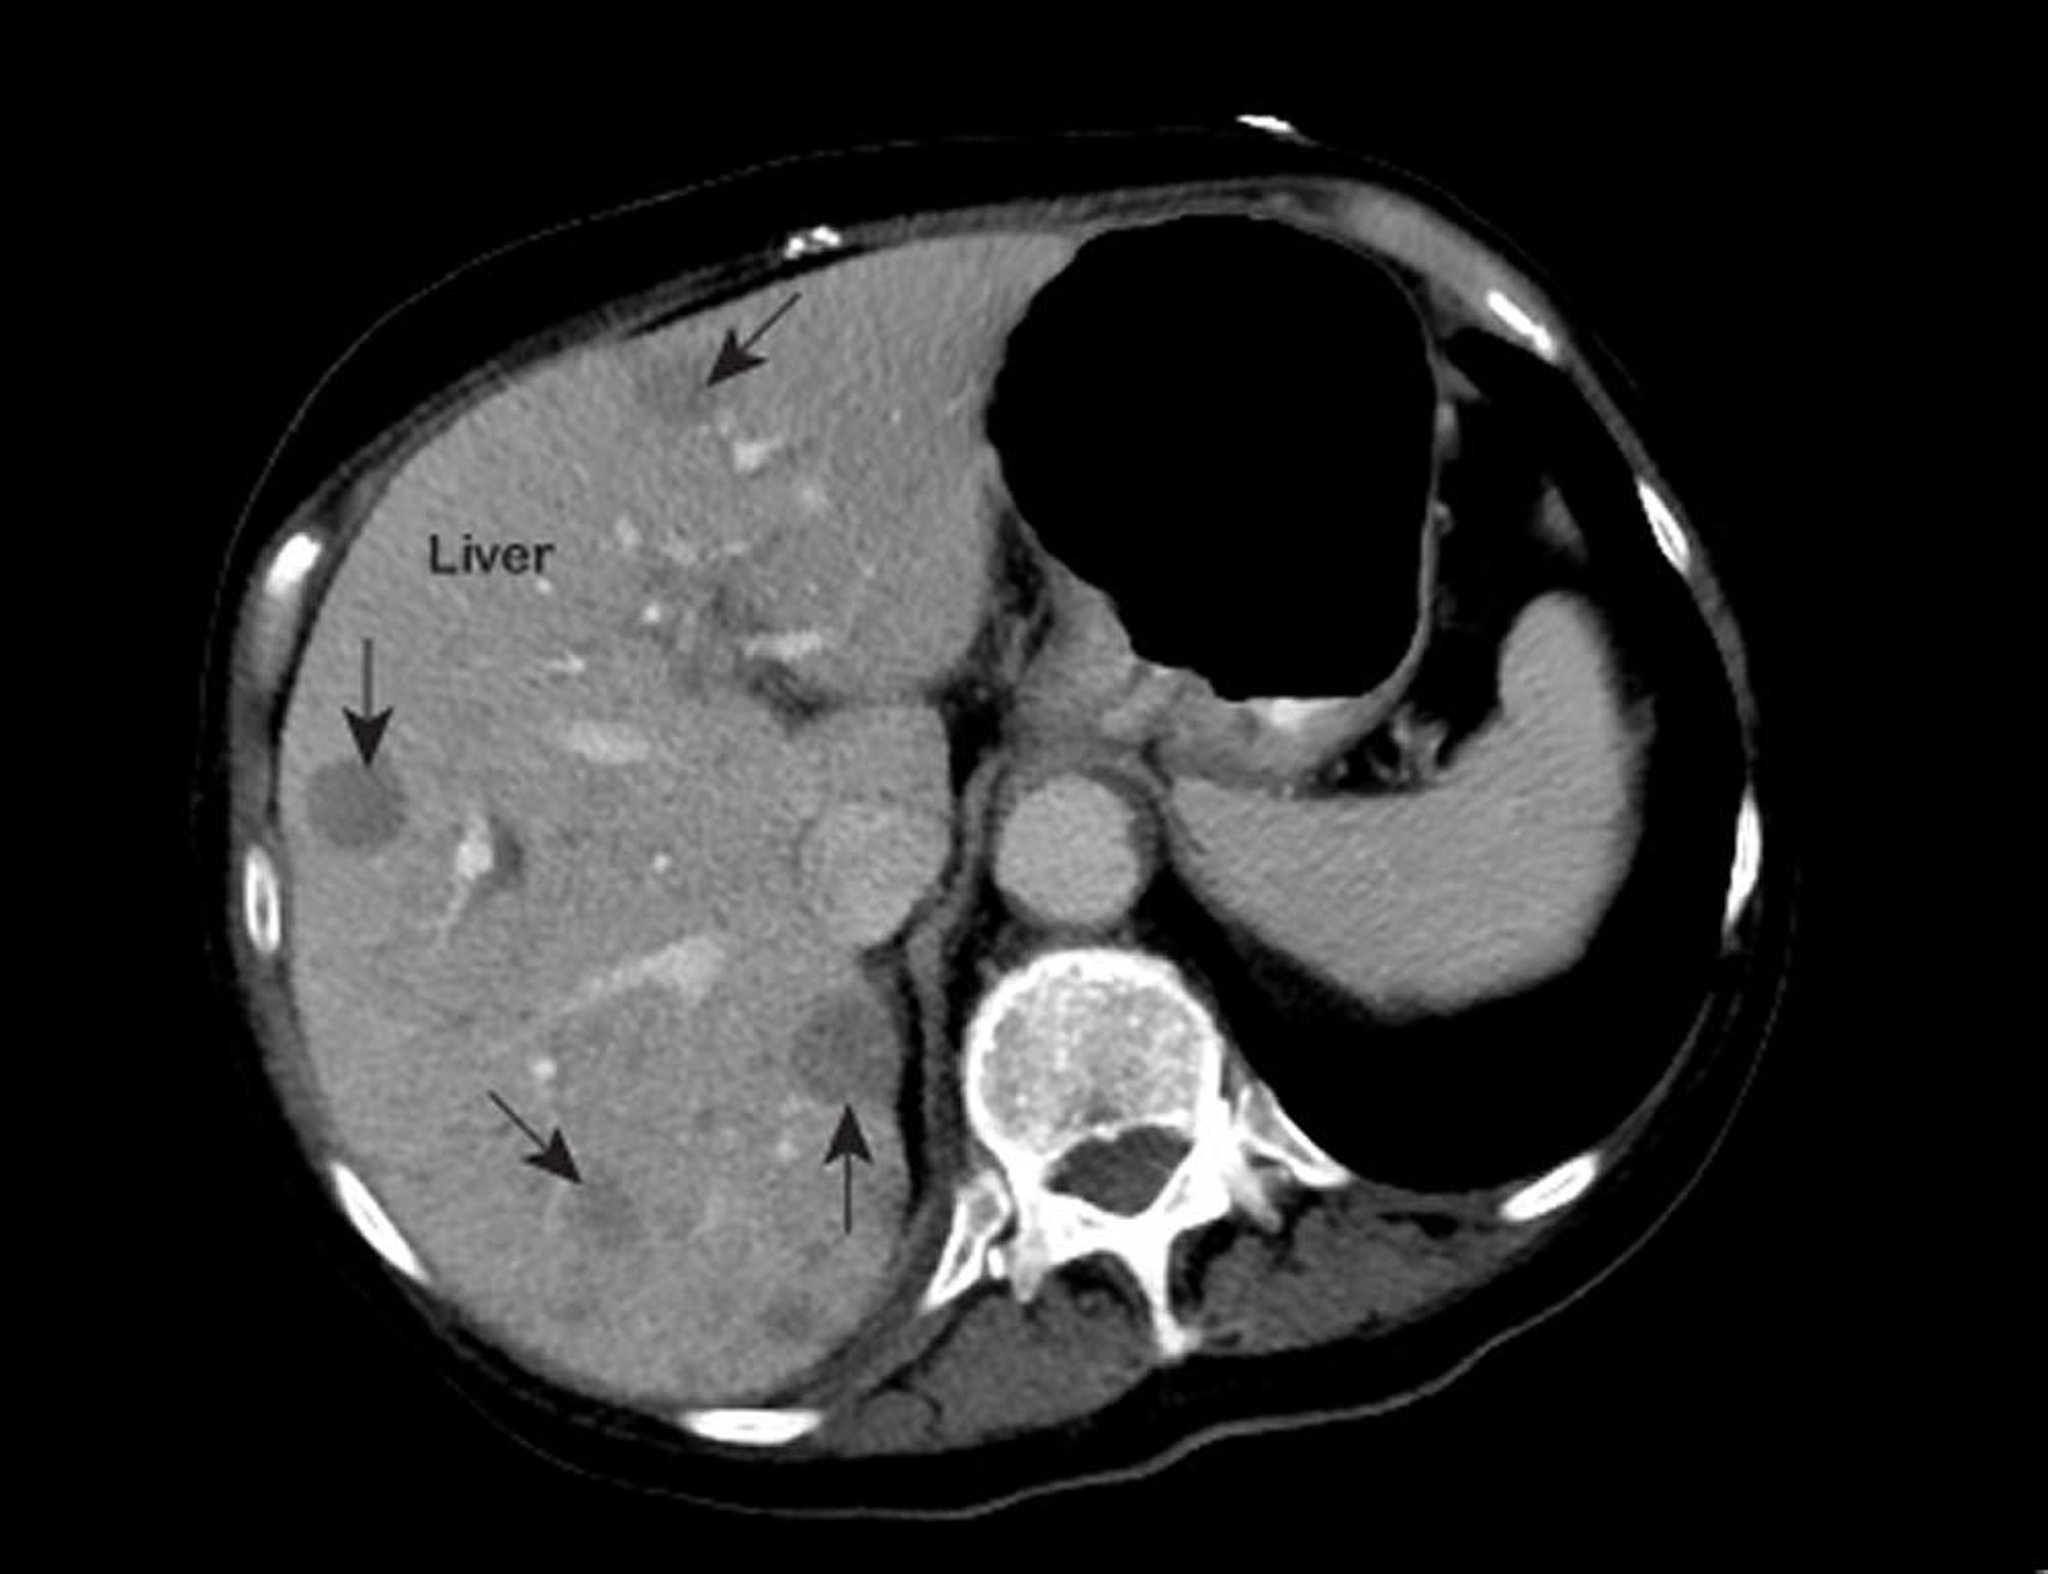

Se il medico sospetta un tumore epatico, si effettuano test epatici, semplici esami del sangue per valutare il grado di funzionalità del fegato e i risultati possono essere anomali, come accade in molte altre patologie. Quindi, questi riscontri non possono confermare la diagnosi. Di solito, è utile l’ecografia, ma la tomografia computerizzata (TC) e la risonanza magnetica per immagini (RMI) del fegato sono generalmente più accurate nel rilevare il tumore. Prima di effettuare la TC o l’RMI, di solito si inietta un mezzo di contrasto in vena che facilita la visualizzazione di anomalie eventualmente presenti (vedere Esami di diagnostica per immagini del fegato e della cistifellea). Tuttavia, gli esami di diagnostica per immagini non sempre riescono a rilevare tumori di piccole dimensioni o a distinguere il tumore dalla cirrosi o da altre anomalie.